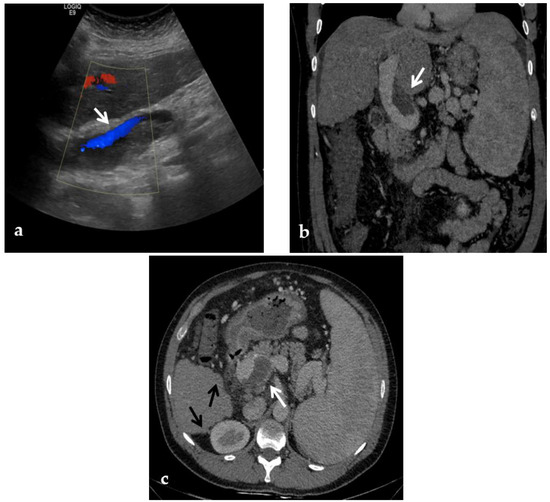

Figure 3.

Color-Doppler Ultrasound and CT images of portal vein thrombosis in a 54-year-old male suffering from liver cirrhosis. (a) Color-Doppler Ultrasound image shows a narrow hepatopetal flow (arrow) despite a large endoluminal thrombus in the extrahepatic portal trunk. (b) Portal phase coronal CT image shows the lack of luminal enhancement and increased portal vein caliber due to a large endoluminal thrombus in the extrahepatic trunk (arrow). (c) Portal phase axial CT image shows the extension of the portal vein thrombosis up to the splenomesenteric confluence (white arrow); liver cirrhosis is visible on the the liver surface that presents lobulated margins (black arrows).

A CT scan in the pre-contrast phase can show hyperattenuating material in the portal vein. After contrast injection, lack of luminal enhancement increased portal vein caliber, increased arterial hepatic enhancement, and decreased portal hepatic enhancement are typical findings of PVT [28] (Figure 3 and Figure 4). Transient hepatic attenuation differences related to altered hepatic perfusion can also be demonstrated on CT with geographic areas of increased attenuation at the periphery of the liver on arterial phase imaging. These transient attenuation differences are related to decreased portal venous perfusion and compensatory increased arterial perfusion from the periphery of the liver [46,49].